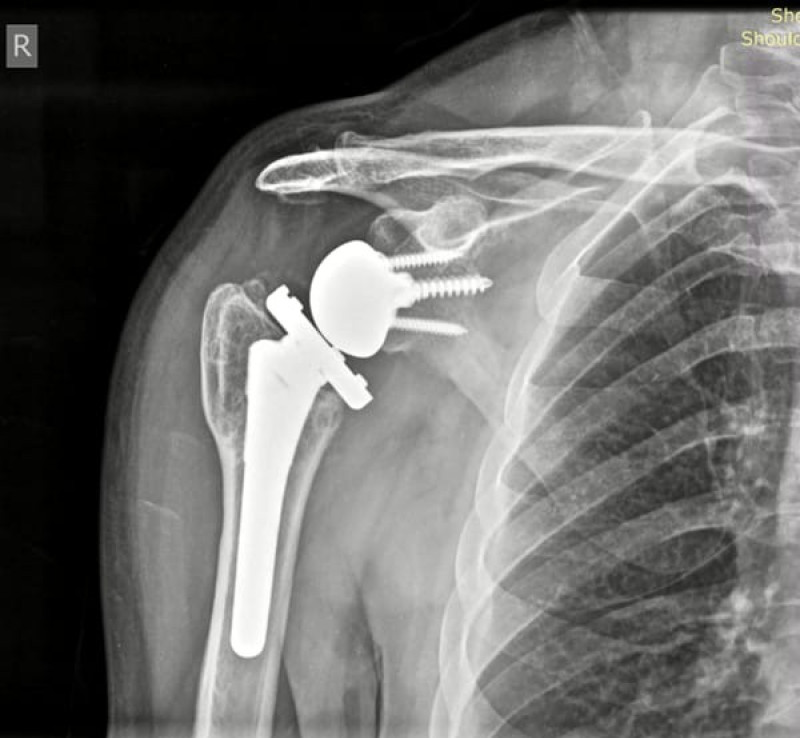

După o evaluare amănunțită, inclusiv investigații imagistice complexe, diagnosticul a fost confirmat: artroză post-traumatică severă și necroză avansată de cap humeral. Afecțiunea era atât de avansată încât nicio formă de terapie conservatoare nu mai era aplicabilă.

Dr. Cosmin Faur, medic primar ortoped, a propus o soluție chirurgicală modernă: artroplastia totală cu endoproteză inversată. Deși puțin cunoscută în România, această tehnică se bucură de recunoaștere internațională pentru eficiența ei în cazurile complexe.

Artroplastia totală cu endoproteză inversată este o intervenție chirurgicală modernă, recomandată în cazurile în care articulația umărului este grav deteriorată, iar tratamentele clasice, respectiv medicamentele, infiltrațiile sau fizioterapia, nu mai dau rezultate. Se adresează în special pacienților cu artroză avansată, necroză de cap humeral, așa cum este și cazul domnului P. și unde osul s-a distrus ca urmare a lipsei de vascularizare, sau în cazul unor rupturi mari ale coafei rotatorii”, menționează medicul ortoped.

Această proteză schimbă mecanica articulară: bila artificială este fixată pe omoplat, iar cupa concavă pe osul brațului. Astfel, pacientul poate mișca din nou brațul folosind mușchiul deltoid, chiar dacă ceilalți mușchi nu mai funcționează.

La primul control, pacientul avea o mobilitate redusă la jumătate (...) La 6 săptămâni după operație putea ridica brațul la 170 de grade - o dovadă a eficienței acestui tip de protezare inversă”, subliniază dr. Faur.